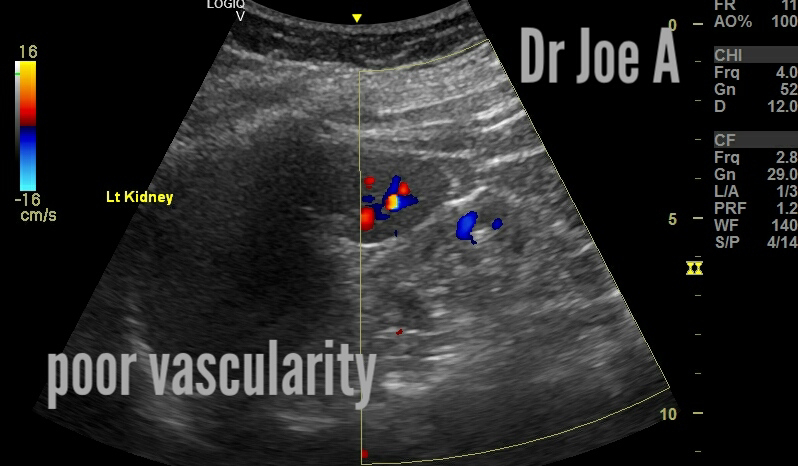

All the signs of medical renal disease involving the left kidney.

The left kidney is barely visible on ultrasound.

Color Doppler shows poor vascularity.

So here the list of ultrasound findings in this case:

The left kidney appears smaller in size than the right kidney.

The kidney tissue appears more echogenic (brighter) than normal, which may indicate the presence of scar tissue or an increase in fat content.

The normal boundary between the outer (cortex) and inner (medulla) regions of the kidney appears indistinct, suggesting a loss of cortico-medullary differentiation.

Blood flow to the kidney is reduced, as evidenced by a decrease in renal artery size and flow velocity.